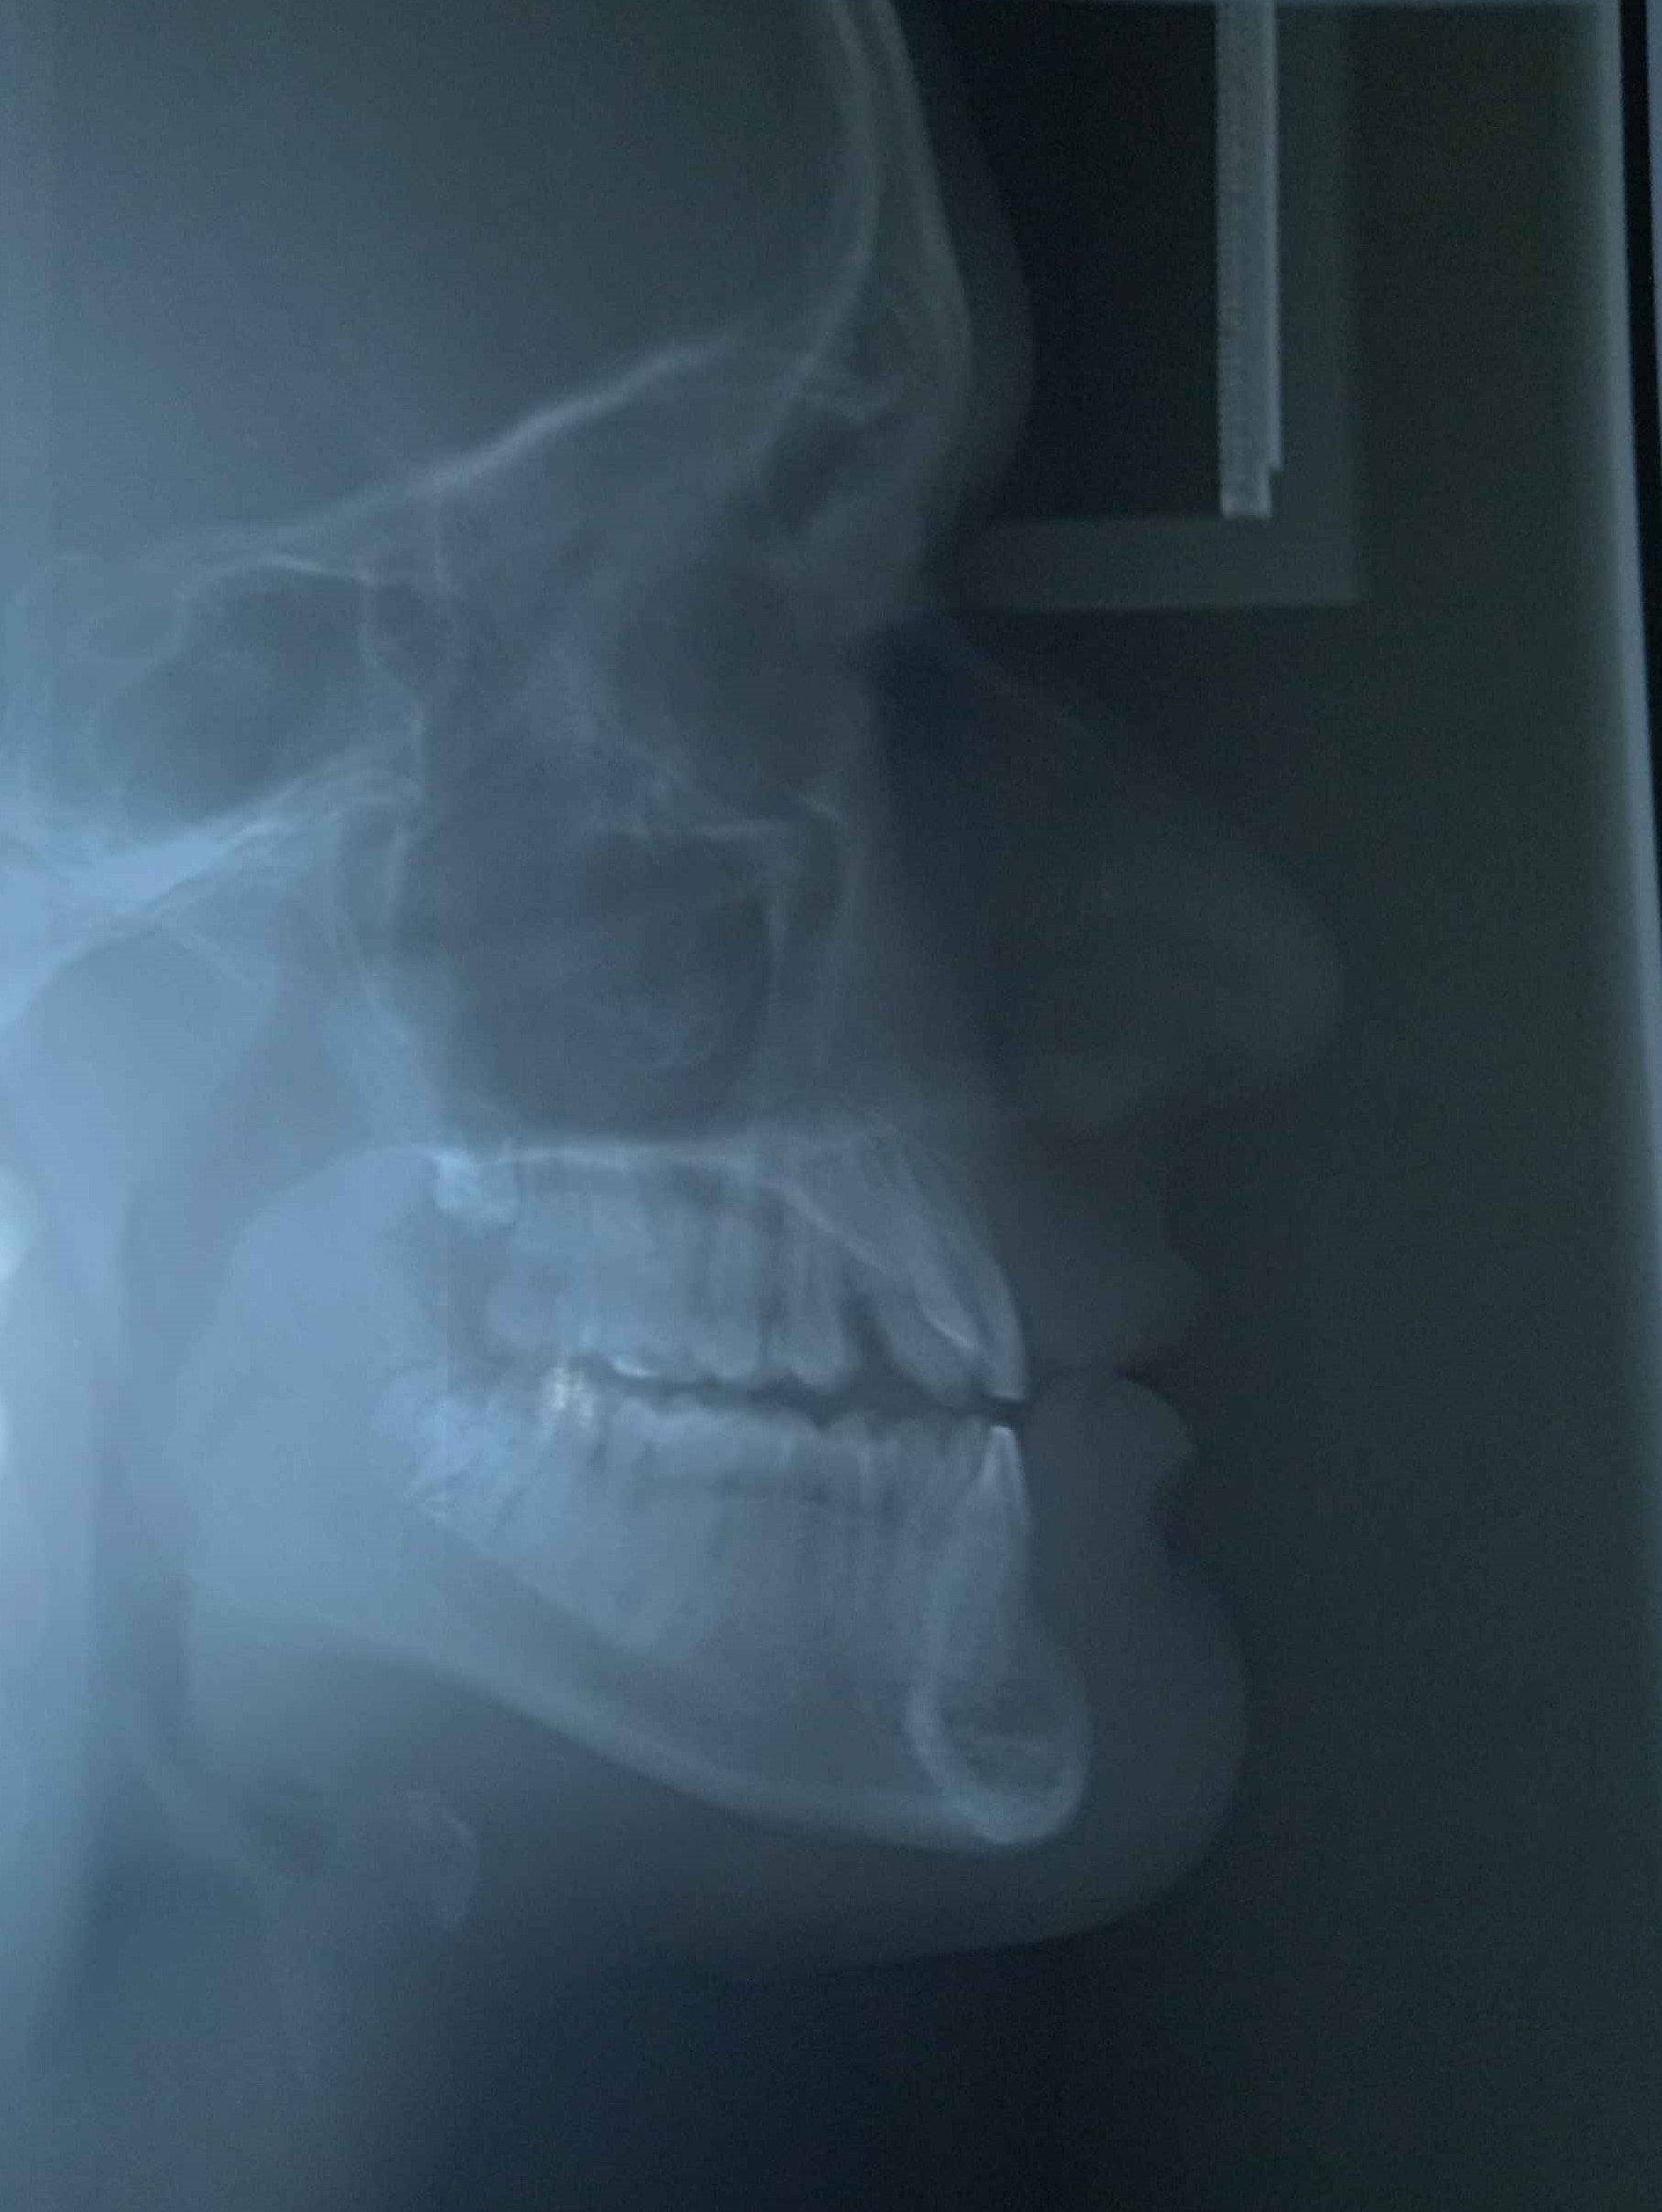

Lower jaw

Upper jaw

I have hypodontia i had all baby teeth as a kid and when those fell out 2 of adult teeth never came back and i have to do double jaw surgery at 18 i am 16 now but in a few days i have to get braces and the dentist is around 50 y old so he is old school and he wants to take a few teeth out of my lower jaw and i told him i cant do that i dont want a smaller lower jaw he just smiled and said i can teach him when i finish dental school and i dont know yet if they will widen my maxilla in surgery too or just push it forward if they wont i think i need palate expander too but idk what to say to him so he does something else then pull my teeth out also i cant go to another dentist bcs only this clinic does this type of stuff and he is the boss of that clinic also i cant go to private one they wont do surgery too i tried 3 private ones and they all send me to the same clinic. Help i have apointment with him tommorow. I forgot but also i was thinking of asking for bone grafting since i think he wants to take lower teeth out to make my lower jaw smaller to match my small upper jaw should i ask for that i dont think i have enough bone for implants.